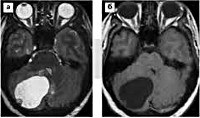

Q85 Факоматозы, не классифицированные в других рубриках